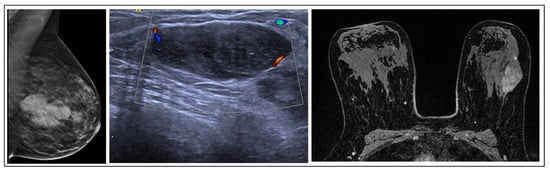

RSs usually appear on mammography as a spiculate lesion or a region of structural distortion with a radiolucent core, sometimes accompanied by calcifications. Tomosynthesis aids in identifying RSs on mammograms [19]. The appearance can vary on ultrasound, ranging from no distinct correlation to a hypoechoic irregular mass. Moreover, MRI findings may exhibit variability and lack specificity. RSs may present without any MRI correlation, displaying no enhancement, or manifest as mass lesions with irregular margins or non-mass enhancement [20]. These imaging characteristics require caution, as RSs can resemble invasive breast cancer (Figure 3). Histologically, central fibroelastosis is surrounded by compressed glandular structures and cysts, sometimes associated with benign or malignant changes [21].

Figure 3. RS radiological features.